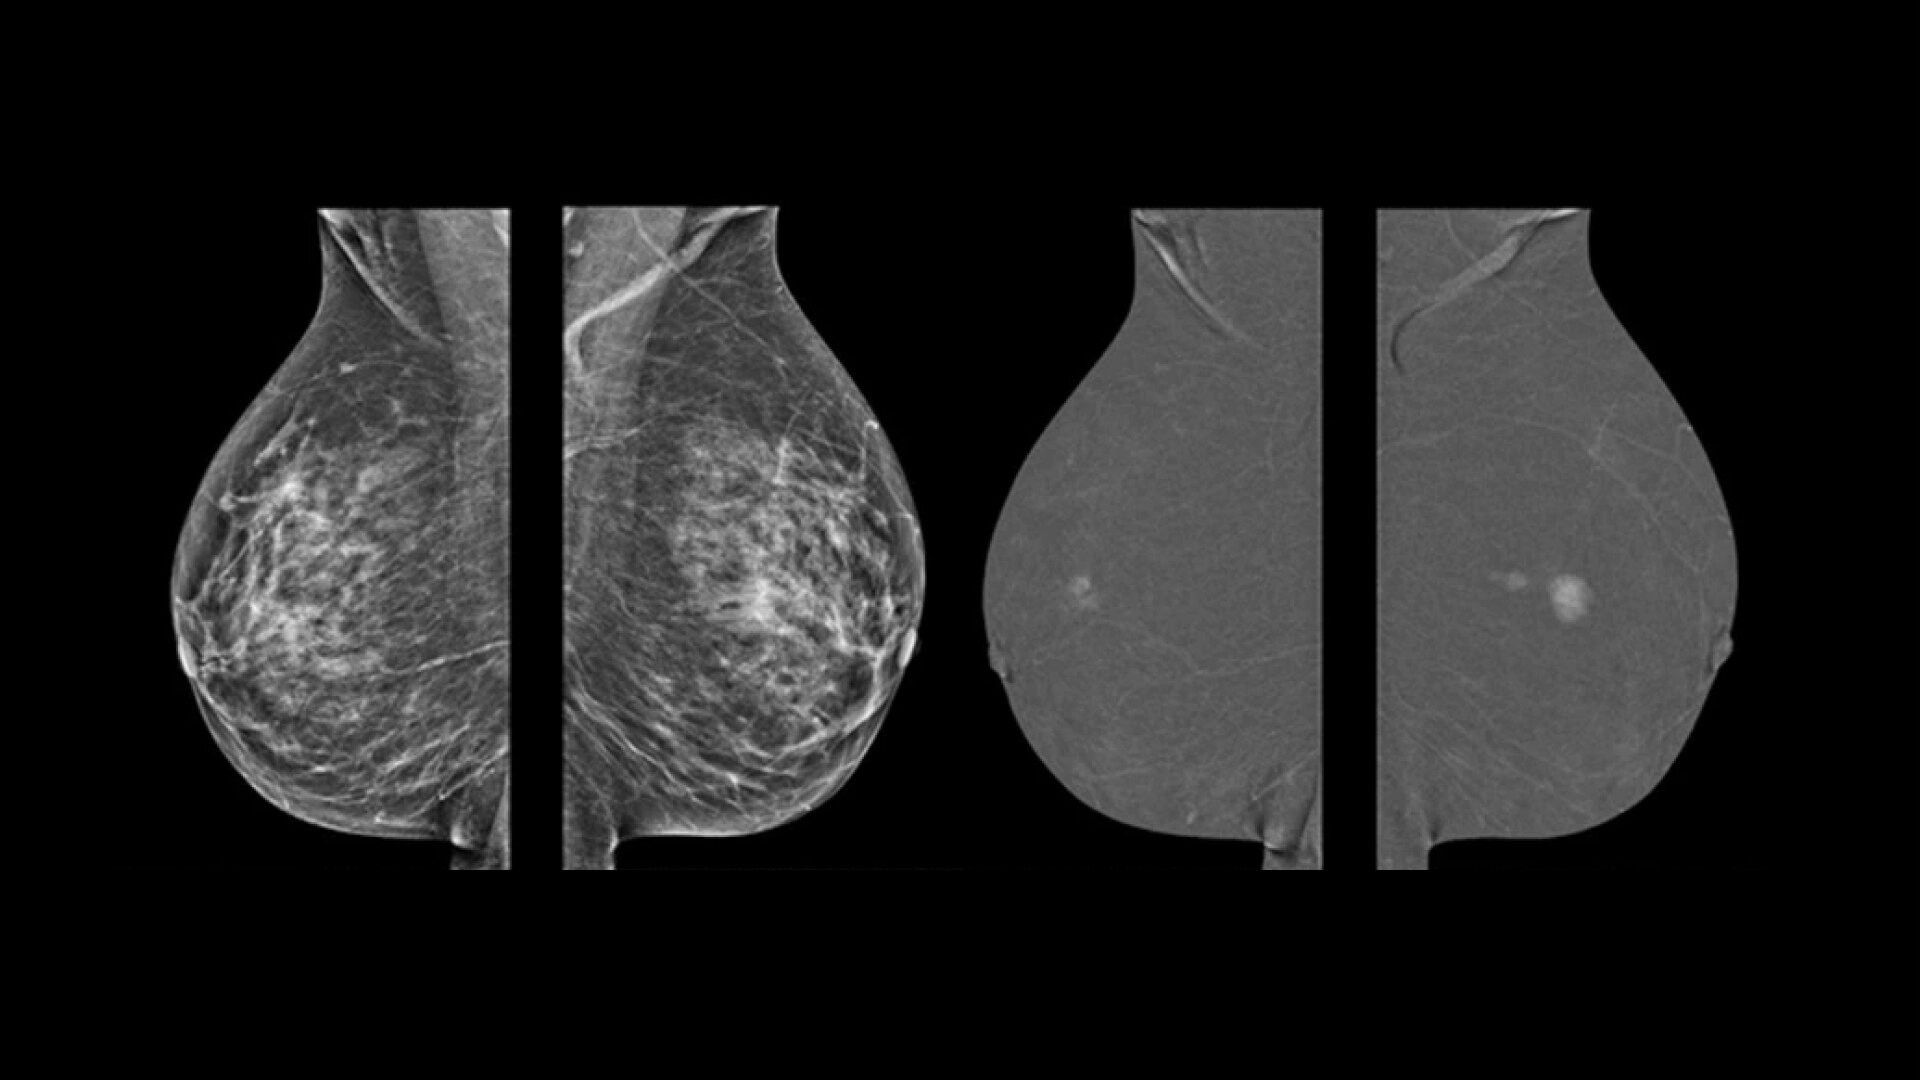

• Find lesions that cannot be seen on routine mammography6,7,8.

• Provide high specificity for low false-positives1.